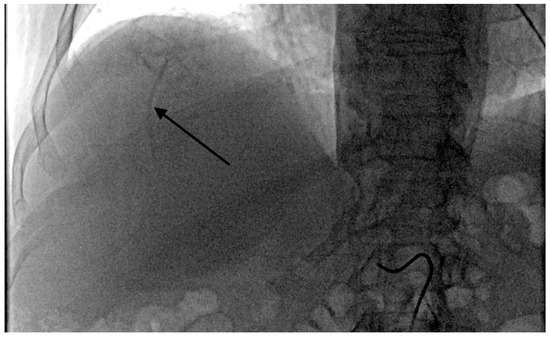

- Grade 3 stasis. Embolizate contrast in subsegmental vessels (Figure 3).

- Grade 4 stasis. Embolizate contrast in segmental vessels (Figure 4).